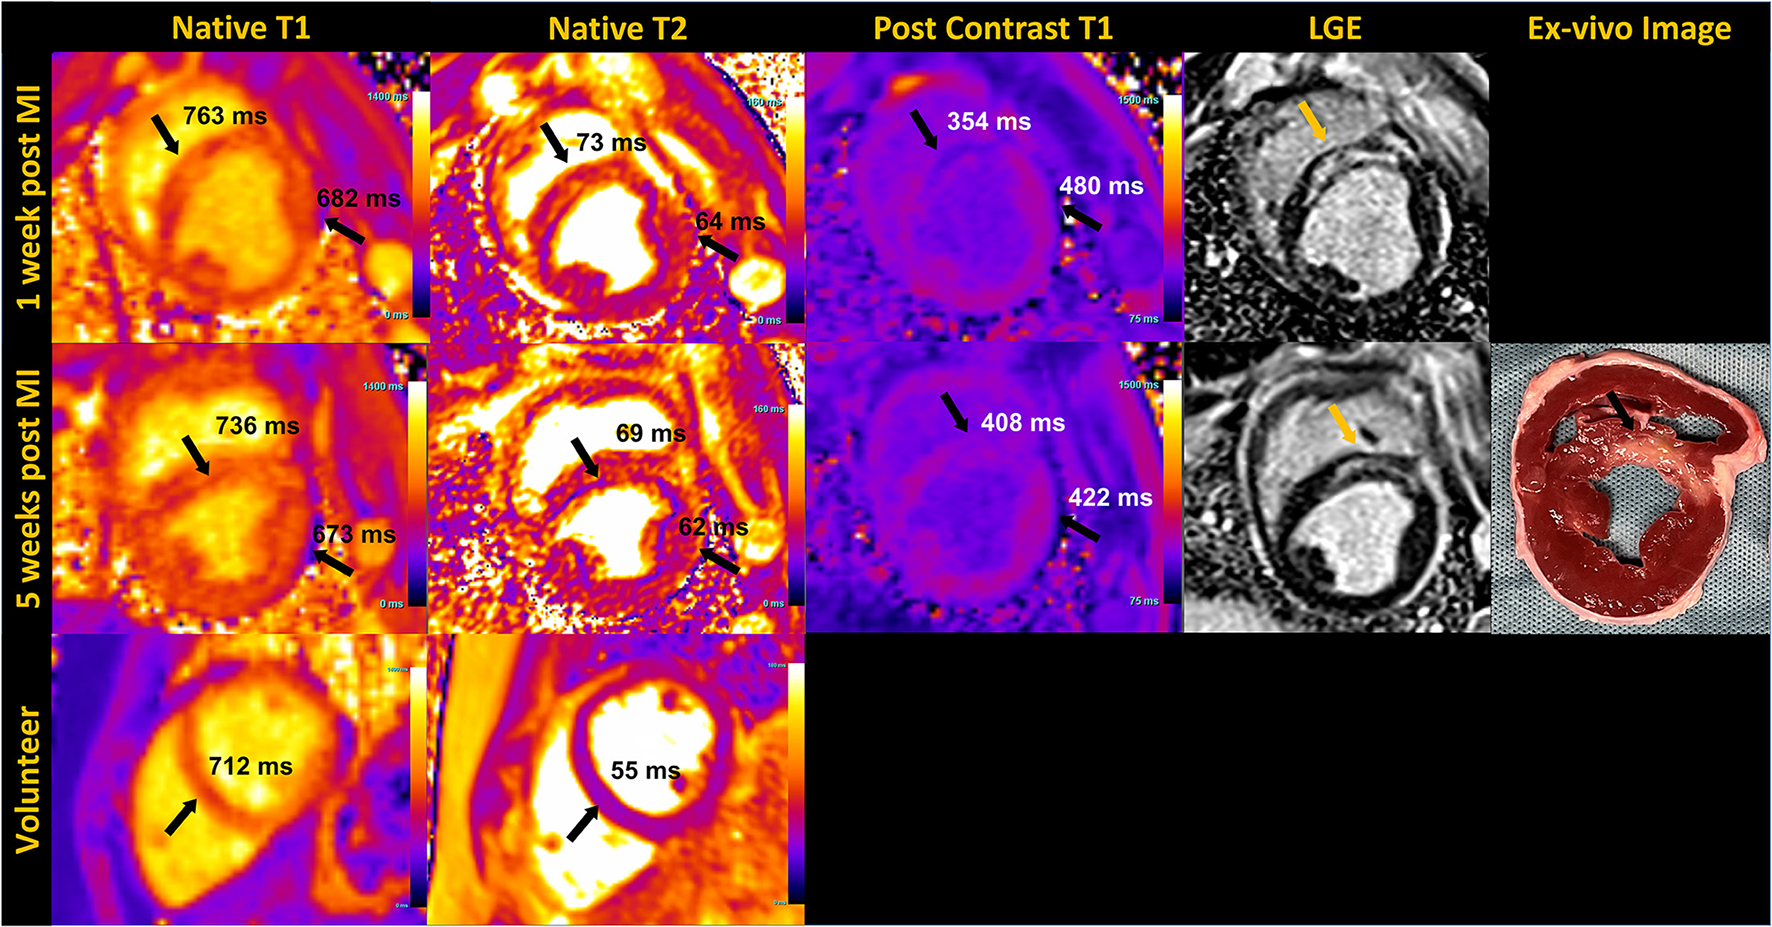

The application of T1 and T2 mapping sequences were investigated in both healthy volunteers and a porcine infarct model (Figure 6). Post-contrast T1 was shorter and native T2 was higher in infarct regions compared to remote myocardium during the acute stage post-MI in the animal images shown. As prolonged breath-hold durations could be tolerated in the animal studies, we incorporated additional source images into the T1 (30 images, 60 HB) and T2 (12 images, 45 HB) mapping protocols, with the intention to increase the SNR through effective averaging. Such extended acquisition times would only be feasible in human subjects during free-breathing while employing an effective strategy for respiratory motion compensation.

Figure 6

Mid short-axis quantitative myocardial native T1, T2 map, post contrast T1 map and phase sensitive inversion recovery late gadolinium enhanced (LGE) images in an animal at 1 week and 5 weeks post-myocardial infarction (MI) are shown in the top two rows. The arrows pointing to the septum on T1 and T2 maps indicate elevated native T1 and T2, and reduced post-contrast T1 corresponding to infarct location, confirmed by LGE and the unstained ex-vivo image. T1 and T2 values of the remote myocardium in the lateral region are also indicated. Sub-endocardial rim artifact are seen on the maps due to the animal's high heart rate. The bottom row shows native T1 and T2 maps acquired in a healthy volunteer in the mid-short axis view.

Our preliminary assessment of T1 and T2 mapping at 0.55 T demonstrates feasibility, but still requires considerable investigation for clinical translation. The extended breath-hold of 14 to 16 HB we implemented for the volunteers may be too long for cardiac patients. Ringing artifacts resulting from the poor temporal resolution (~250 ms) were observed in some T2 maps, as shown in the porcine images. In some instances, these artifacts extended across the septum, resulting in lower T2 measured in the septum compared to the lateral wall. In addition, the motion correction algorithm used routinely with success at higher field has been challenging at 0.55 T, most likely due to the low SNR of the individual source images. In instances where the motion correction did not perform well, deformation of the individual motion-corrected images resulted in blurring of the myocardial boundaries in the resulting maps. Further research into optimal image registration and motion correction strategies are ongoing.